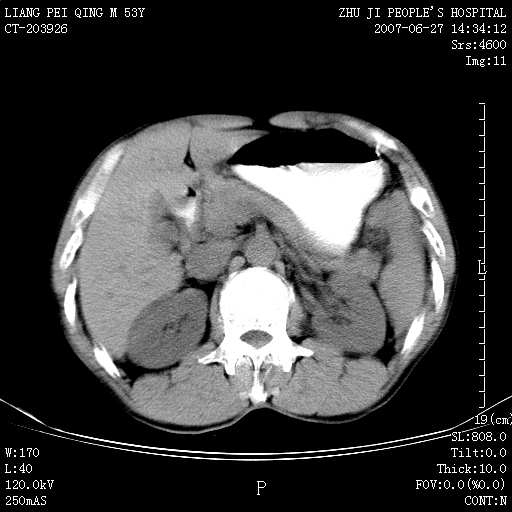

以下是引用余辉在2007-6-27 18:46:00的发言:[br]病灶多发,内可见大片状低密度区,病灶病灶等密度区轻度强化,动脉期后期病灶低密度区与高密度区对度增加,考虑1淋巴瘤2转移瘤3血管内皮细胞瘤(不知有否静脉期及延迟期扫描)

以下是引用zzzzhhhhaaaannnn在2007-6-27 20:44:00的发言:[br]脾脏 肋骨转移可能性大,下腔静脉内有癌栓

以下是引用狙击手在2007-6-28 10:35:00的发言:[br]1:定位:来源于脾脏。2:强化:强化,但不均匀。3:下腔静脉癌栓?下腔静脉充填不均匀与增强时间有关,延时即可明确。4:肋骨破坏?看起来并不确切。综上考虑几个最常见诊断:1;淋巴管瘤;2;血管内皮肉瘤(高度恶性,早期即可转移,常见肝,肺,骨)3;转移瘤(无特征性,只有肝或其它腹腔脏器有类似病变时,才可提示之)